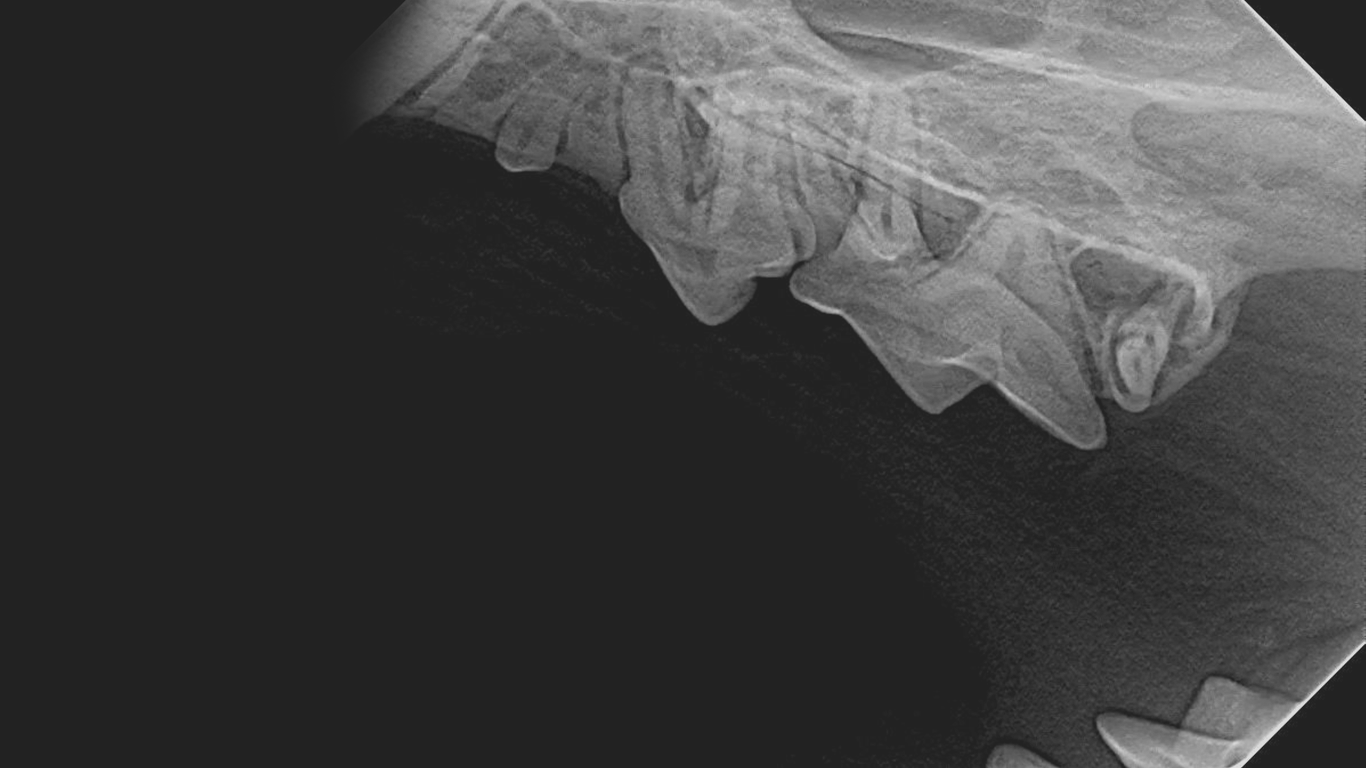

The patented shape eliminates stopping points where damage often occurs, distributing biting force and allowing the tooth to slide off the sensor.

Capture better diagnostic images with the market’s smallest pixel pitch (14 µm).